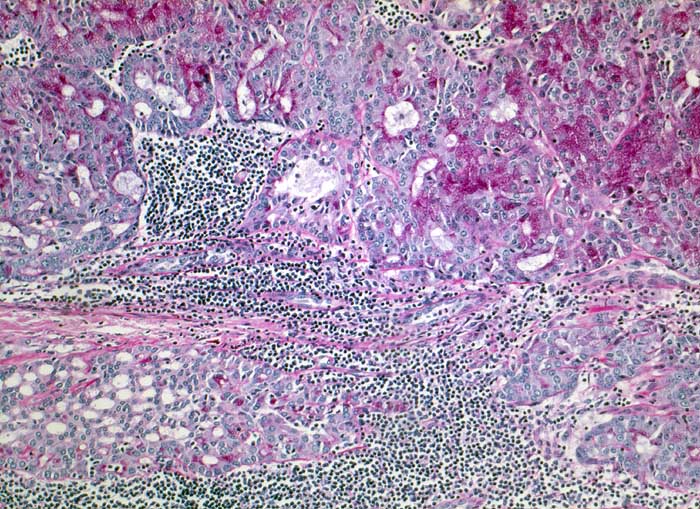

Azinuszellkarzinom der Parotis

Azinär differenzierte Tumorzellen mit reichlich Diastase-PAS positivem Zytoplasma. Teils follikuläres, teils mikrozystisches Wachstumsmuster. Reichlich lymphoides Stroma.

Tumorzellen fokal Amylase und Diastase-PAS positiv

Azinuszellkarzinome sind nach den Mucoepidermoidkarzinomen und den nicht näher spezifizierten Adenokarzinomen die häufigsten malignen Speicheldrüsentumoren und am häufigsten bilateral (3%). Azinär differenzierte Zellen können oft nur eine Minderheit ausmachen. Daneben gibt es auch kubische Zellen vom Streifstücktyp oder Zellen eines Adenokarzinoms ohne spezielle Differenzierung. Azinuszellkarzinome können viele Wachstumsmuster zeigen: mikrozystisch, solide, follikulär, papillär zystisch, glandulär. Typisch, aber nicht spezifisch ist ein ausgeprägtes lymphoides Stroma (keine echten Lymphknoten), welches zur richtigen Diagnose führen kann. Die Azinuszellen enthalten Diastase PAS positives Material und sind immunhistochemisch positiv für Amylase (oft nur herdförmig).